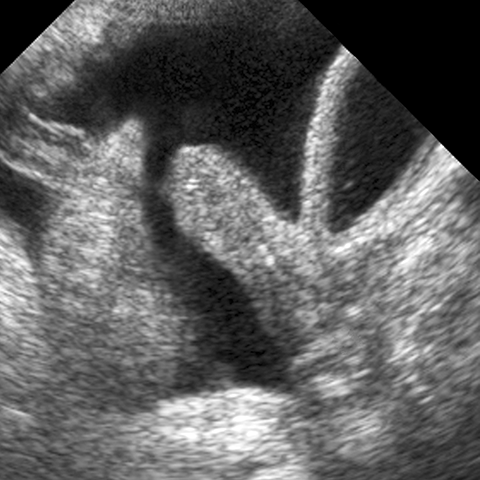

Female Reproductive Organs, Ultrasound [5 of 5]